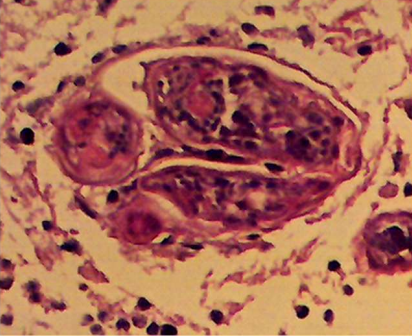

In nine patients the histopathology slides showed schistosomal ovae surrounded by inflammatory cells namely lymphocytes, eosinophils and edema .

Image (10) Three Schistosomal ova, one cut in cross section inside a vein. The Mirasidia are viable as indicated by the well-preserved nuclei of the parasite

Image (11) there is a single Schistosomal Ova (arrow) at the bottom surrounded by a chronic inflammatory cellular infiltrate. The Mirasidium is dead as indicated by the smudgy nuclei. The deep blue color is probably due to calcification. The lesion is in a Virchow-Robin space